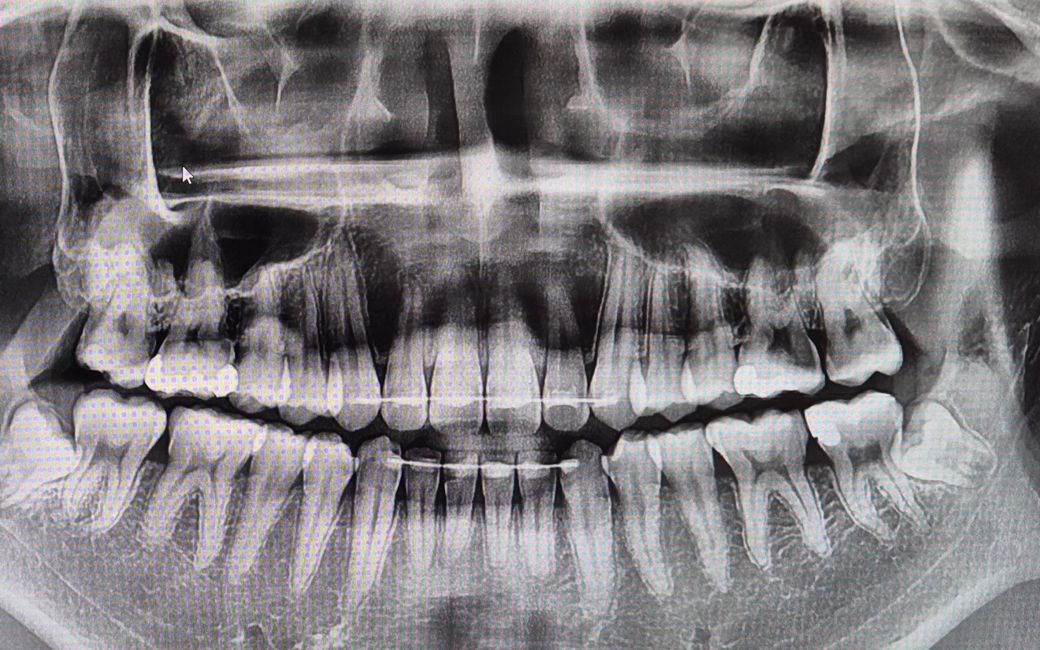

엑스레이 찍었는데 비중격만곡 맞나요??

• 코가 처음사진처럼심해게 비중격만곡이라 6개월전에 비염수술 받고 코뼈도 정상적으로 해주셨다고 들었어요.

근데 치과가서 엑스레이 찍었는데 이거봐도 좀 굽은 거 같은데 재발한건가요...?

• 1번 째 사진

CT 단면 사진으로만 봤을 때에는 약간의 비중격 만곡증이 있는 것으로

보이는데 이것이 정면 사진도 같이 확인이 필요한 것으로 보이며 만곡증의

정도가 심하지는 않아 재 수술이 필요하지는 않을 것으로 보입니다.

걱정이 많이 되시겠습니다만, 두개의 영상 사진이 전혀 다르며, 저 CT와 엑스레이만으로 평가하는 것도 아닙니다. 궁금하시면 수술하셨던 병원 가셔서 재진 보시면 되겠습니다.

비중격만곡에 대한 교정 수술을 하더라도 비중격의 좌우 대칭이 완전히 일치하지는 않습니다. 비중격만곡 교정술을 시행한 것으로 보이는 흔적이 관찰되며 상기 소견으로 보아 비중격만곡증이 다시 재발했다고 보기는 어렵습니다. 답변이 도움이 되었기를 바랍니다.